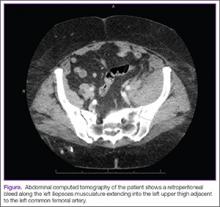

Laboratory evaluation was significant for anemia with decreased hemoglobin (Hgb) from patient’s baseline; subtherapeutic international normalized ratio; and elevated partial prothrombin time and partial thromboplastin time. (The Table lists the patient’s complete laboratory results on admission to the ED.) Computed tomography (CT) with oral and intravenous contrast was initially ordered, but the patient refused the oral contrast. Based on her body habitus, the decision was made to proceed with the CT scan without oral contrast. The CT of the abdomen and pelvis showed a small-to-moderate-sized retroperitoneal bleed; a 2.2-cm low-density lesion was also visualized in the left kidney. No diverticulitis or signs of inflammation were noted (Figure).The patient was admitted to the hospital with a request for cardiology and surgical consultations. Upon inpatient admission and evaluation, the warfarin and enoxaparin were stopped, and the surgical team elected for conservative management of the retroperitoneal bleed. The patient had stable Hgb levels on serial complete blood-cell counts.